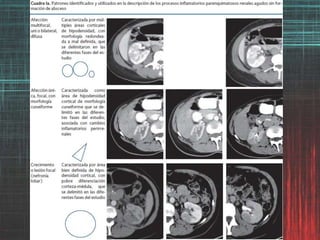

Hallazgos por imagende los procesos inflamatorios del trayecto urinario. La PXG es una variante infrecuente (<1%), atípica y severa de infección parenquimatosa renal. Debido a que sus manifestaciones simulan una neoplasia, el diagnóstico preoperatorio es difícil y si no es considerado por el médico radiólogo como una posibilidad, es referido como un hallazgo incidental por el cirujano o como un reporte de patología.

Hallazgos por imagende los procesos inflamatorios del trayecto urinario. Valor clínico de la graduación de la Pielonefritis aguda (PA) basada en hallazgos de TC -afección parenquimatosa- como factor predictivo de severidad y evolución de la PA. Grado 1 Sin afección demostrable por TC Grado 2 Afección demostrable por TC menor al 25% Grado 3 Afección demostrable por TC mayor del 25% pero menor del 50% Grado 4 Afección demostrable por TC por arriba del 50% Paick SH, Choo GY, Baek M, Bae SR, Kim HG, Lho YS et al. Clinical value of acute pyelonephritis grade based on computed tomography in predicting severity and course of acute pyelonephritis. J Comput Assist Tomogr 2013;37: 440-442